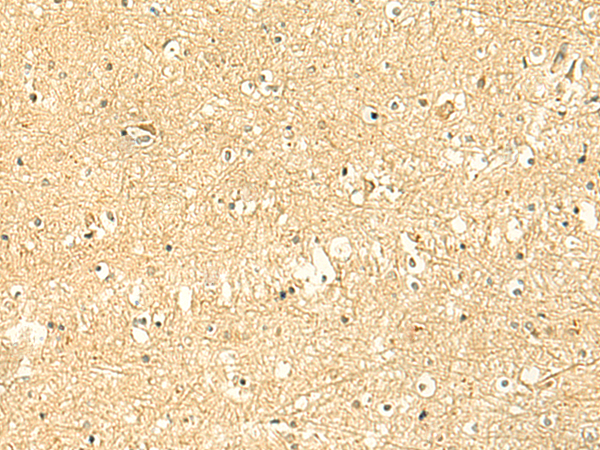

分类: 科研抗体货号: P10087别名: PNAA; PNAD应用: IHC反应种属: Human, Mouse